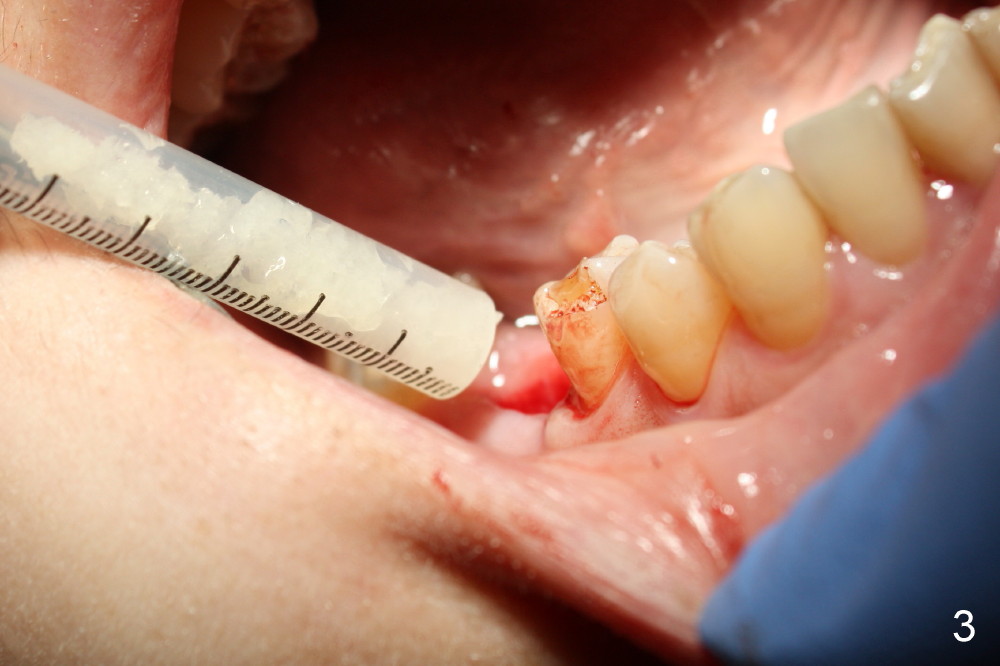

The tooth #30 was extracted in other office 1 month ago. The socket appears to heal normally. A tissue-level implant is placed as planned and smoothly. No antibiotic is prescribed pre- or post-op. The patient reports mild pain 1 week postop. There is a sign of infection. Amoxicillin is prescribed. One week later, the symptom improves, but the infection signs are present (Fig.1). The implant has mobility and is removed (Fig.2). The osteotomy is thoroughly debrided, followed by copious irrigation with normal saline and Clindamycin soaking. Irradiated cancellous bone graft (.5 mg) is placed (Fig.3,4). The wound is covered by collagen plug (Fig.5) and sutured with Chromic gut (Fig.6). Amoxicilin is prescribed postop. One week follow up reveals normal wound healing (Fig.7 (buccal view), 8 (lingual)).